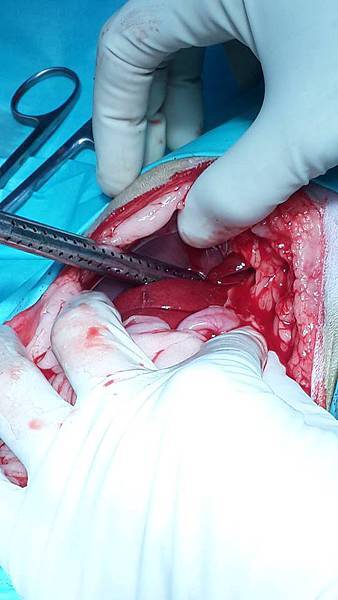

Cleo是一位九個月大的小朋友,媽媽遠從苗栗來找小譚醫師,說Cleo被檢查到橫膈膜破裂,肝臟掉到胸腔扭轉,肝指數已經高到驗血儀器檢查不出來了。

這已經屬於非常嚴重的情況,醫療團隊感快安排手術,手術發現,Cleo已經出血很嚴重血腹,肝臟也整個在胸腔打結,所幸在通力協助下,把破洞的橫膈膜仔細修補,肝臟也解開打結放回原本的位置。Cleo很爭氣的恢復很好,今天回來拆線也都一切正常。